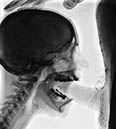

Franks tube